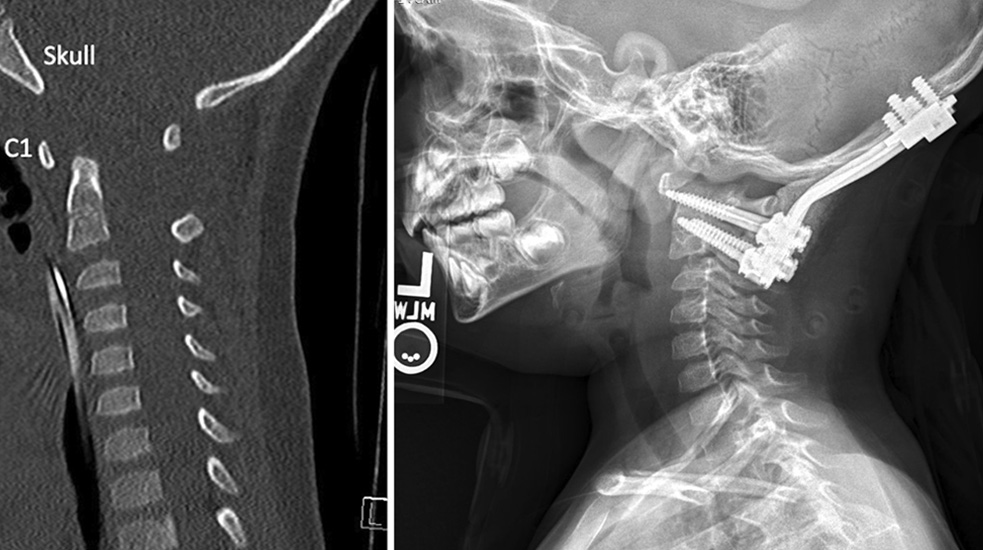

A CT scan image before Owen’s surgery (left) shows increased space between his skull and the C1 vertebra. The second image, a postsurgical X-ray, shows the rods and screws inserted to achieve normal alignment and bone fusion between his skull and spine.

The goal of surgery, Dr. Braga said, was to save Owen’s life by compressing his head toward his vertebrae and undoing the distracting forces acting on the spinal cord and brainstem, reinforcing the spine to hold the skull, and restoring function to his head, neck, and left side.

Dr. Braga used X-ray guidance to continually realign the angles of Owen’s skull to his neck for a natural posture and to avoid damage to his spinal column and the vertebral arteries that move blood between the heart and brain.

Dr. Braga reattached Owen’s skull to his C1 and C2 vertebrae using a plate secured with surgical screws sunk into the skull 6 millimeters deep and then deepened by 2-mm increments until the plate was properly positioned. In the cervical spine, screws were 20 to 26 mm deep into the vertebrae. The skull and cervical screws served as anchor points for implanted rods that extended across the injured segments.

The surgical team then tightened the hardware, which will stay in Owen’s neck forever. Dr. Braga then placed the rib pieces between the skull, C1, and C2. Over time, the bone grafts, skull, and cervical vertebrae will fuse into one long bone that holds everything in place.